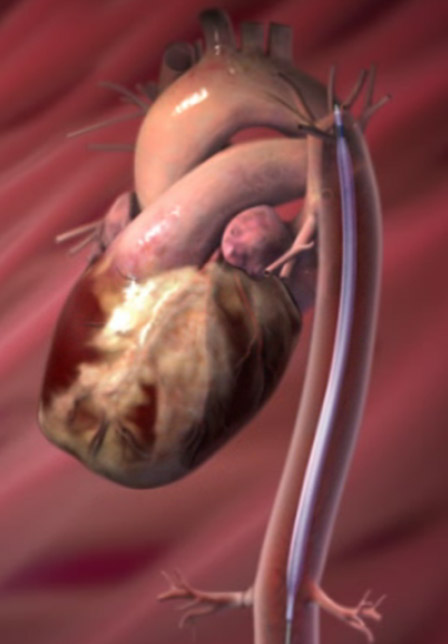

- IABP(大動脈内バルーンパンピング)

- Impella(補助循環用ポンプ)

機械的補充循環装置

下行大動脈内に挿入した大きなバルーンカテーテルを心拍動に合わせて拡張、収縮を繰り返すことによって心臓の補助を行う装置です。

補助循環用ポンプカテーテル(Impella)

左室から大動脈に血流を送り、循環補助、左室補助の役割を果たします。